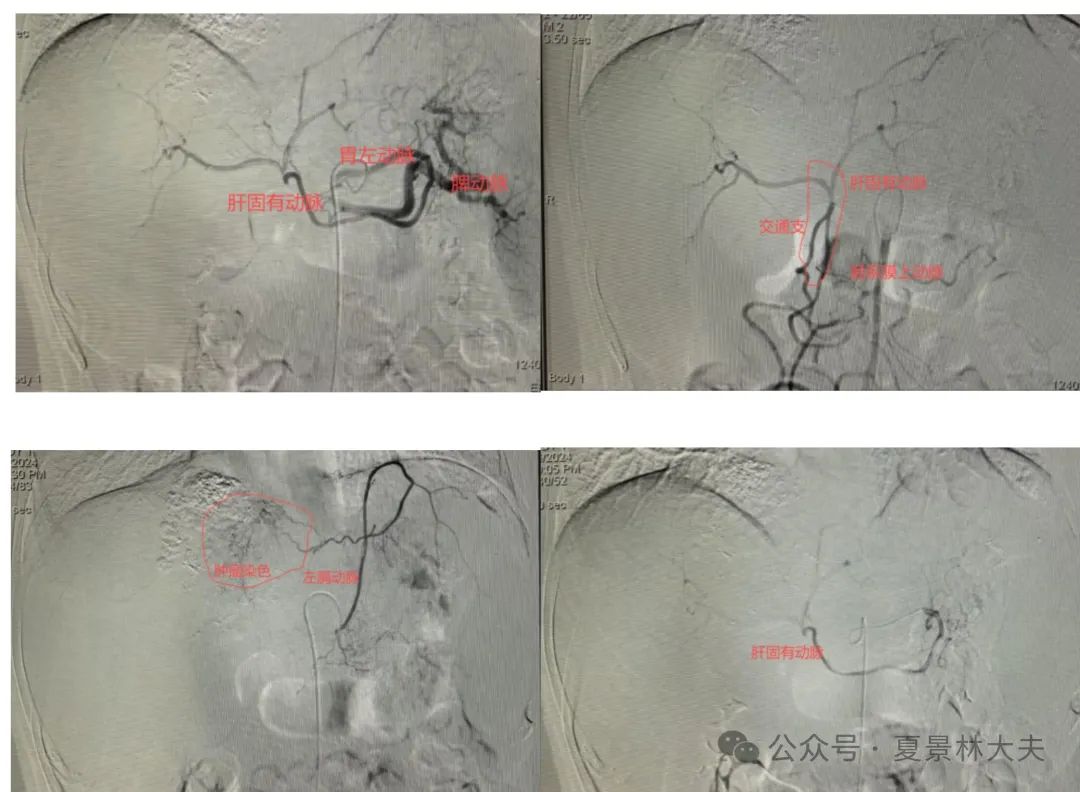

介入手术于入院第二天进行,术中又出现了一个术前无法估计到的难题。肝动脉造影发现:患者肝动脉变异,血管紊乱而复杂,这大大地增加了手术难度(图1)。

图1造影发现肝动脉复杂变异

以下非专业人士可忽略:{腹腔动扭曲未见肝总动脉;肠系膜上动脉发出交通支与肝固有动脉交通;膈动脉发出肿瘤供血分支;仔细读片发现胃左动脉扭曲,跨过腹主动脉再折返回右侧直通肝固有动脉,并与肠系膜上动脉交通支相连。经胃左动脉超选至肝固有动脉后予THP 30mg+碘油10ml、5-FU 0.25g+碘油5ml制成混悬液栓塞,见病灶内碘油沉积较前明显增加;并留置导管于肝固有动脉进行持续灌注化疗(图1)}。

5、难点三:血管变异复杂,超选择困难。术中病人血管扭曲,腹腔动脉分别发出脾动脉、腹腔干,腹腔干发出胃左动脉,胃左动脉再发出肝固有动脉,同时肠系膜上动脉也发出扭曲血管与肝固有动脉交通,膈动脉也发出分支供应肿瘤,总之该病人肝内血管复杂,手术难度高,也考验手术医生的功力和判断力。